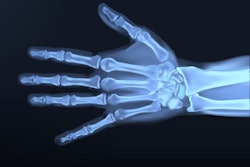

A group led by Baraedi Olaotse of the Botswana International University of Science and Technology in Palapye found that the use of the Greulich-Pyle (GP) atlas -- the most frequently used method for assessing skeletal age around the world -- underestimated ages for males and females in a set of 140 children's hand and wrist x-rays.

The GP atlas was introduced in the 1950s and consists of 1,000 hand x-rays of white people living in Cleveland between the ages of 0 and 18 years old. To estimate bone age, doctors compare a patient's left-hand wrist x-ray with images in the atlas.

To that end, the group collected 140 x-rays from local hospitals for patients between the ages of 5 and 18. Sixty were females and 80 were males. Two experienced readers first derived skeletal age estimates using the GP atlas. This was followed by a comparison between the skeletal age estimates and the chronological ages of the patients.